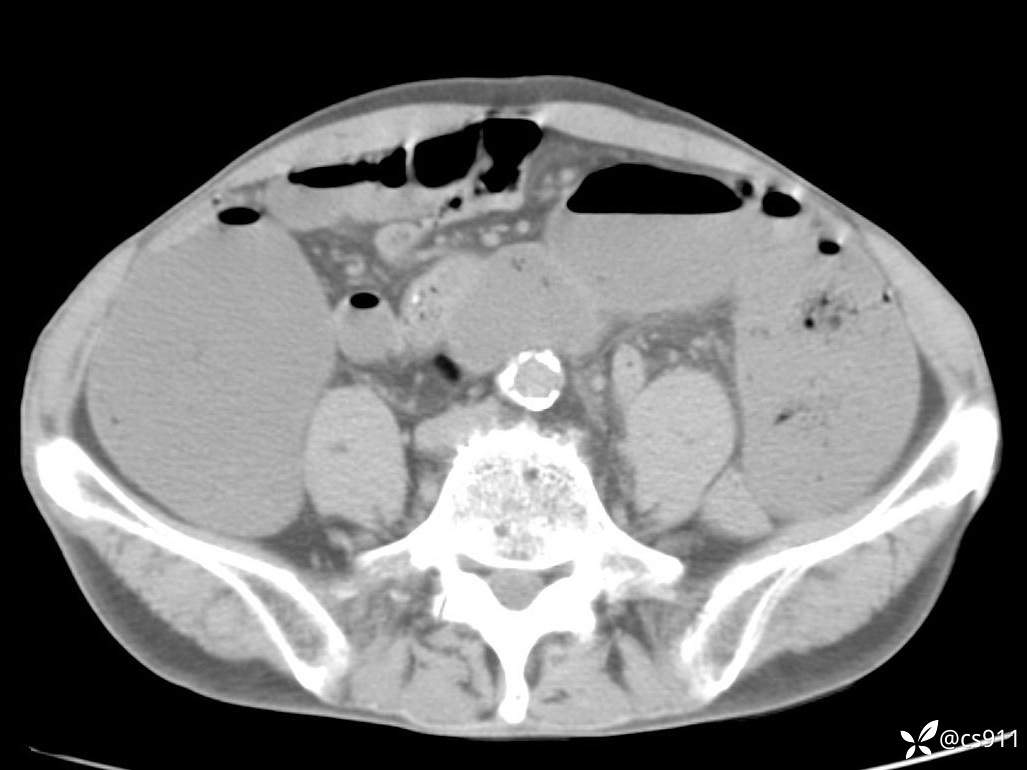

急腹症之急诊CT,原因?答案公布

男,77岁,腹痛、腹胀伴恶心呕吐1天。呕吐胃内容物,非喷射性呕吐,有咖啡色样胃内容物,诉有胃穿孔病史。查体:全腹平,下腹部压痛,全腹无反跳痛,叩诊呈浊音,移动性浊音阴性,肠鸣音减弱,1-2次/分。肛检:直肠未扪及明显肿物,可触及大量粪块。

血淀粉酶(AMY) HH 1859 U/L 35-135